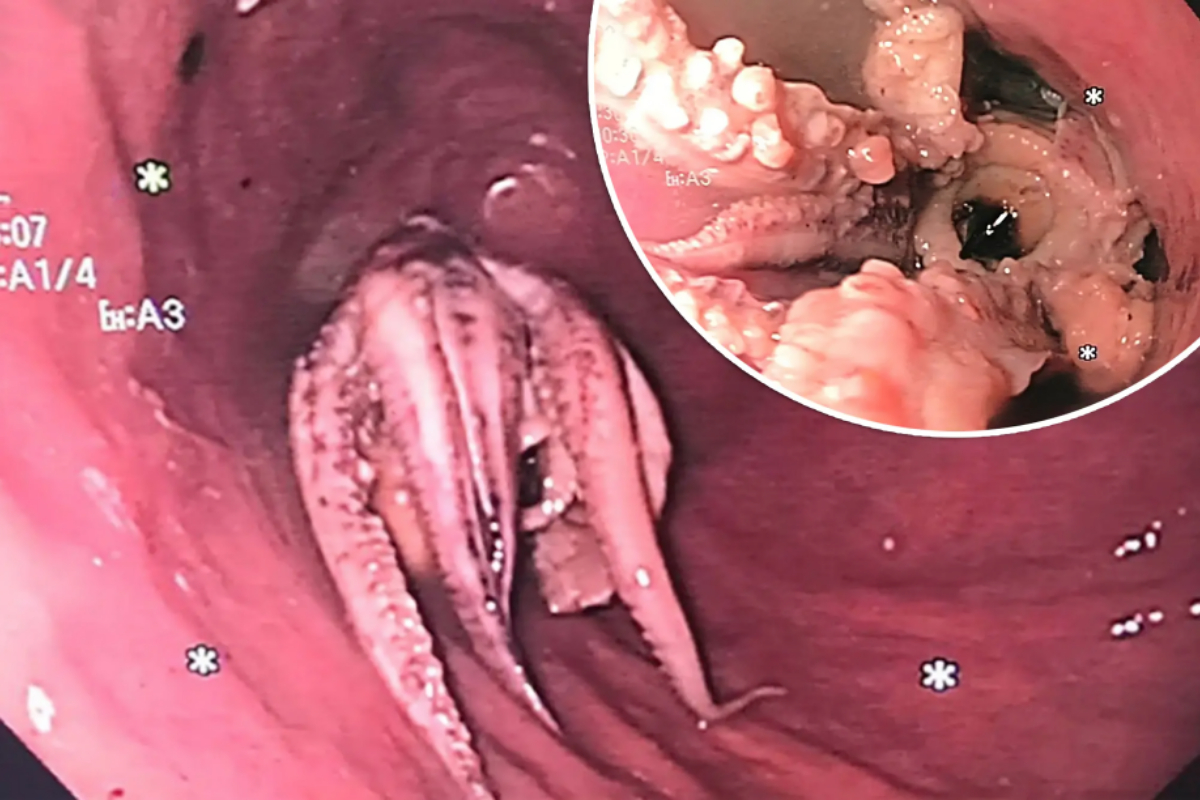

Man’s Esophagus Contains Whole Octopus, Baffling Doctors

Doctors in Singapore were astonished when they found a whole octopus stuck in a man’s esophagus during a gastrointestinal examination. The unnamed Singaporean man experienced vomiting after consuming a meal that included raw octopus. Concerned by his difficulty swallowing, he rushed to the emergency room at Tan Tock Seng Hospital. A CT scan revealed a … Read more